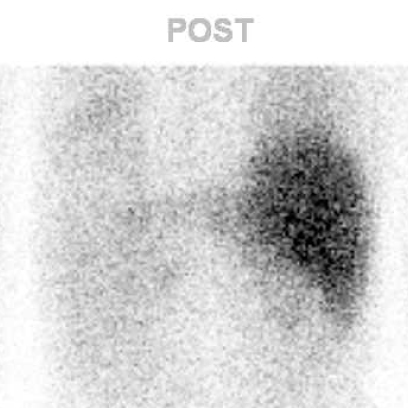

a. 123I-MIBG planar背面像

図2 嚢胞変性した褐色細胞腫